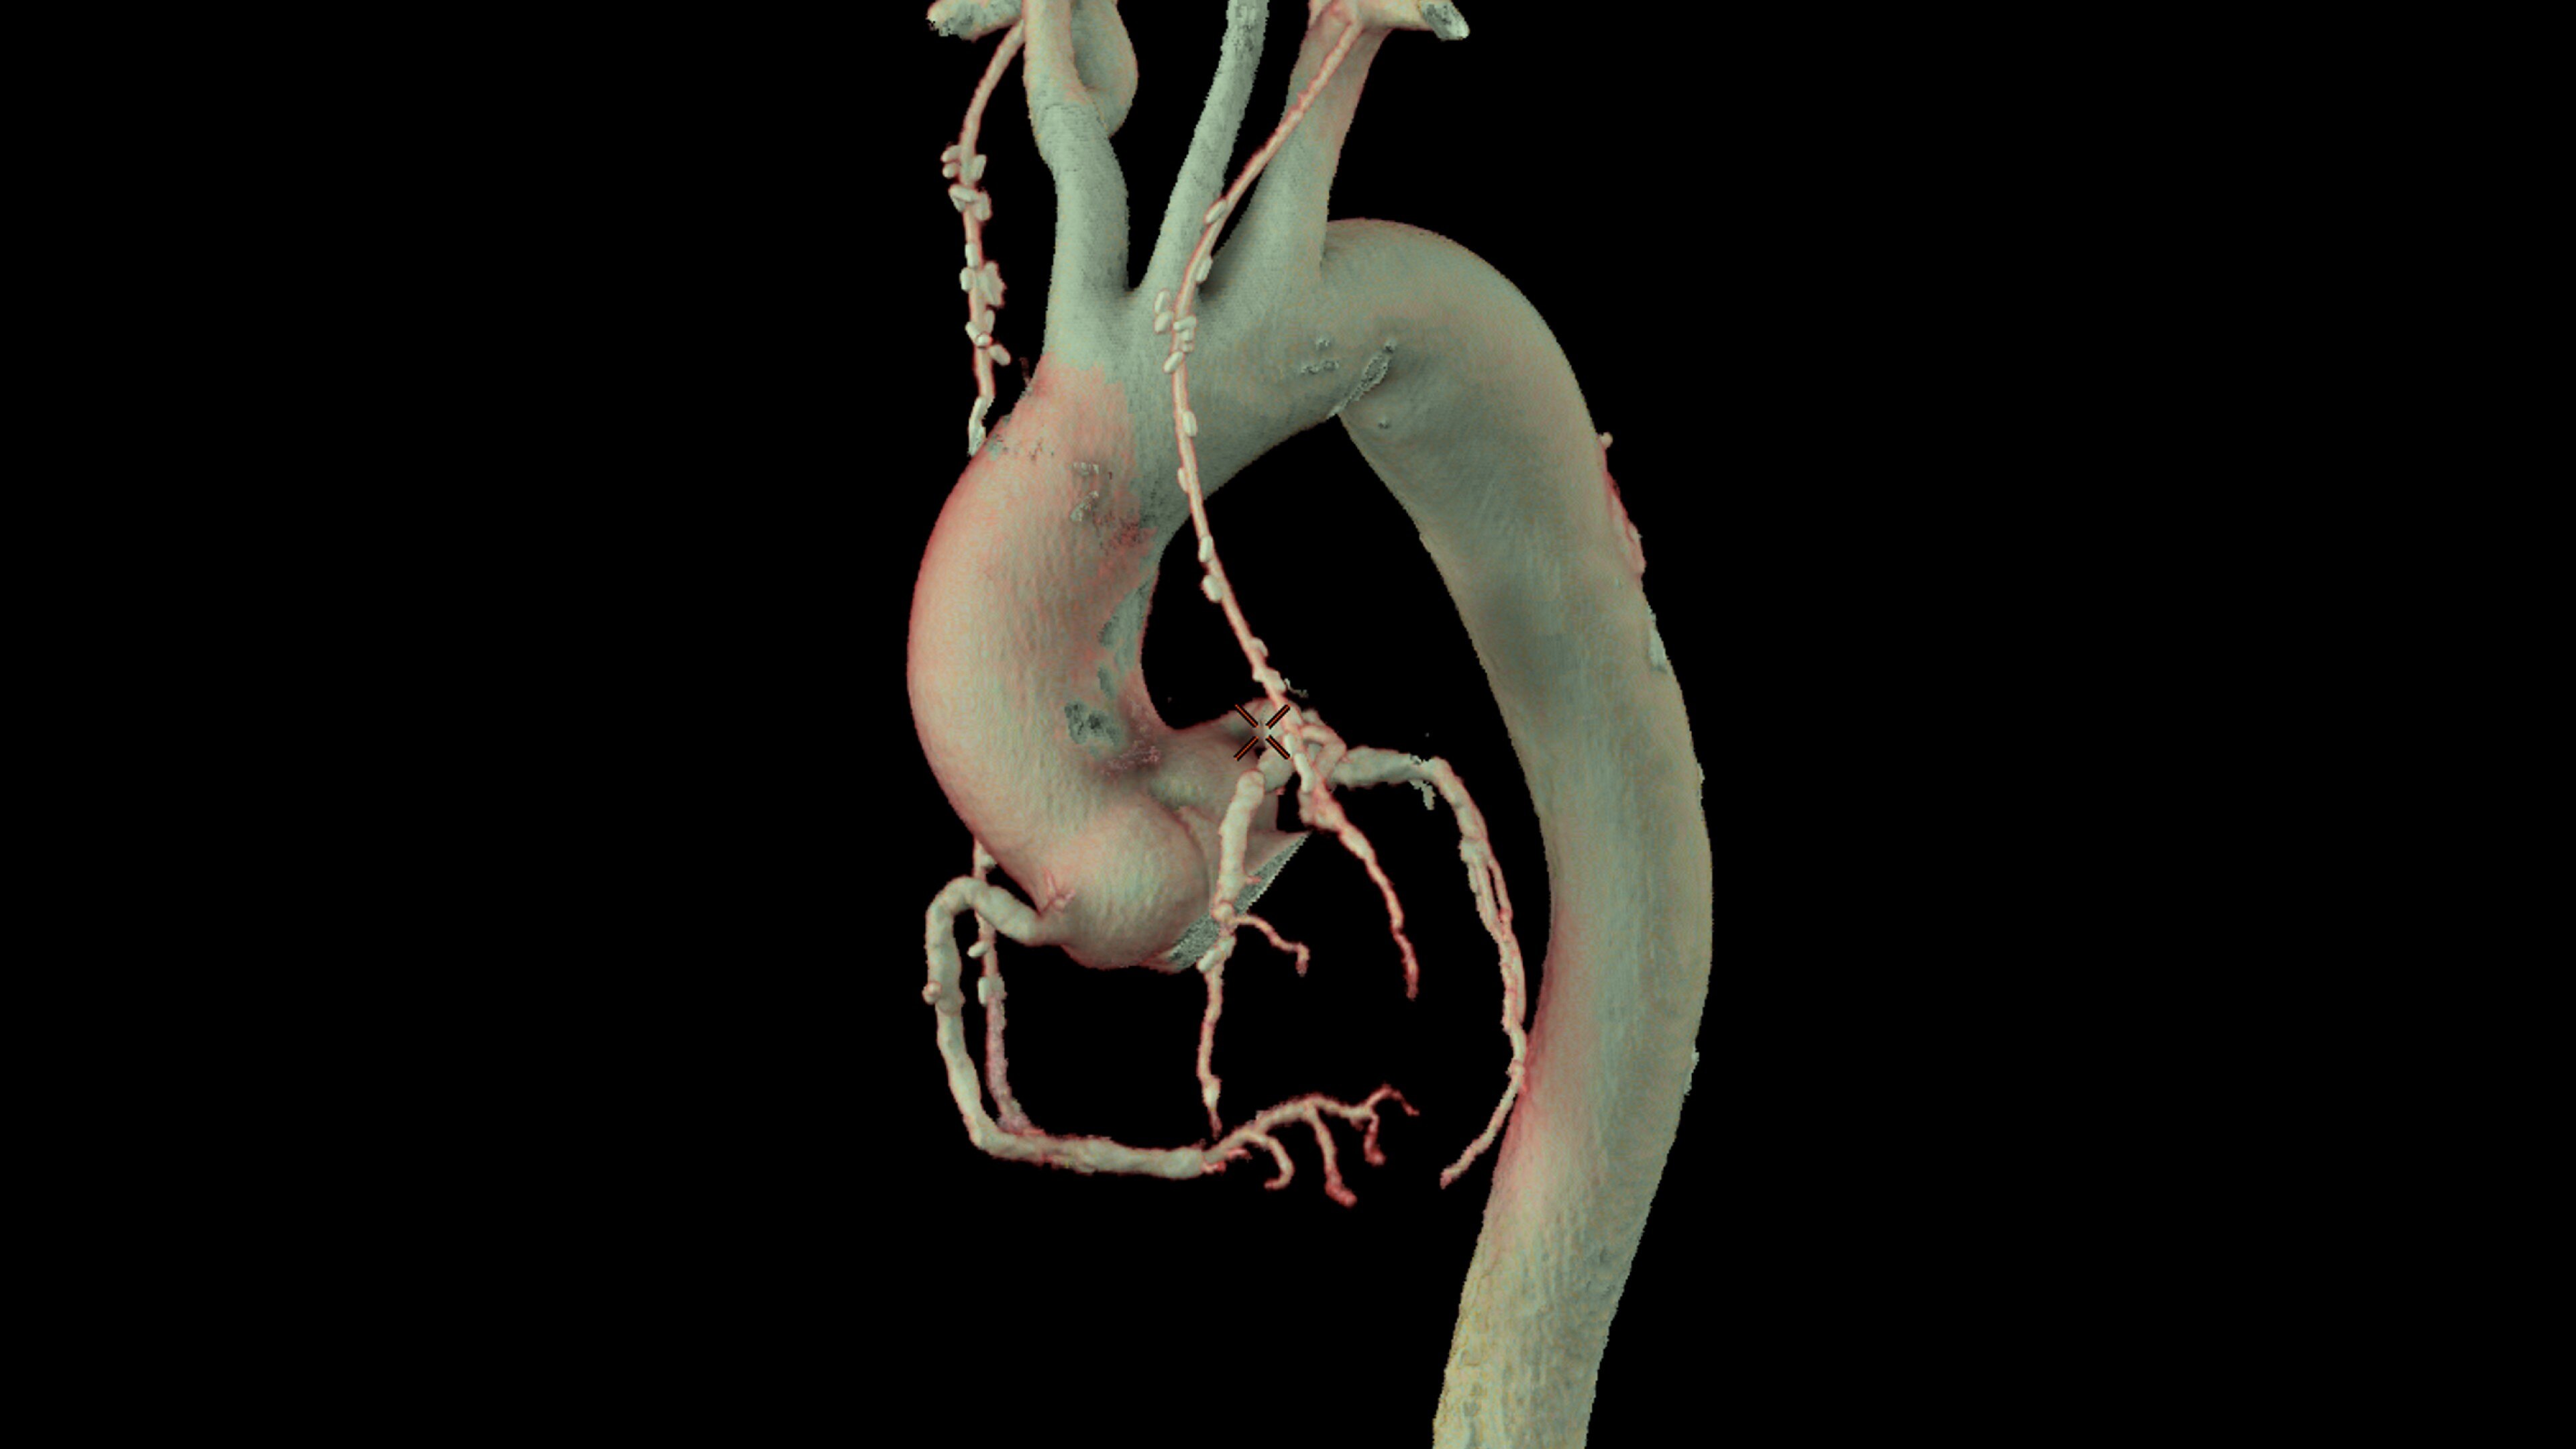

CardIQ Xpress 2.0 Reveal

Bringing integration and automation to your CT Cardiac post processing needs

• Pre-processing automatically recognizes cardiac datasets and performs all segmentations as data arrives on the system saving processing time

• Auto Coronary analysis automatically segments the coronary tree, tracks and labels the coronary arteries

• Three pre-defined orientation protocols for easy review of the coronary vessels and chambers

• Relative perfusion color codes and quantifies percent of hypo-dense areas of myocardium with four selectable color maps and fusion overlays with the coronary tree

• Plaque ID provides volume measurements for four distinct Hounsfield ranges to aid with identification and visualization of coronary plaque

• Automatic extraction of the left ventricle across all phases and the automatic detection of systole and diastole delivers calculated ejection fraction and stroke volumes